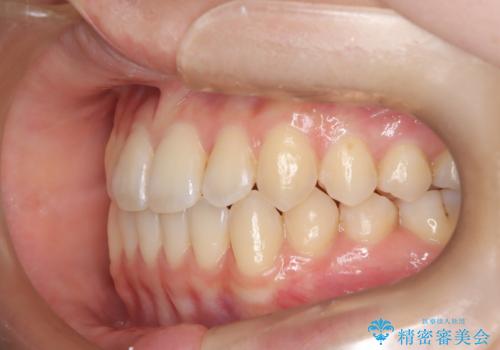

前歯のガタつき、下顎の前突感を治したい インビザライン矯正例

- 治療計画